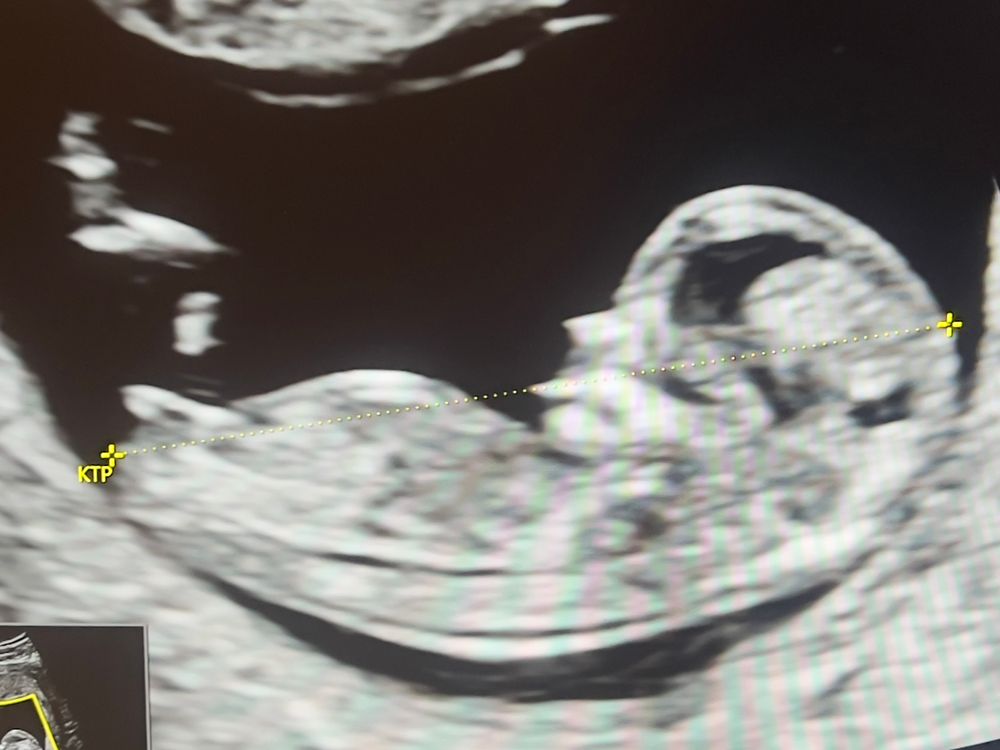

Половой бугорок 12 недель

Девочка это 🌸

22.05.2024

Да, на девочку похоже))

Дама)